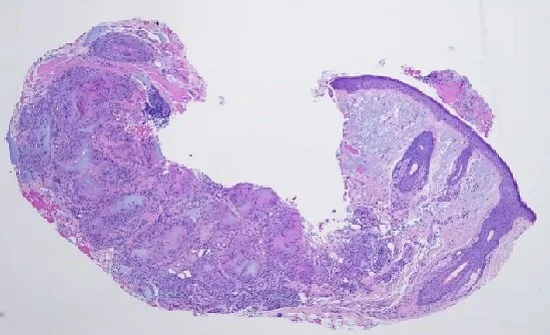

Case 2: Blastic Plasmacytoid Dendritic Cell Neoplasm- An Underrecognoized but Deadly tumor

Caregivers: Aditya Sood UG-2, Dipti Anand MD; Smyrna, GA; Atlanta, GA

History: A 72 year old Caucasian male presented with acute onset of non-palpable, purpuric patches on left anterior proximal upper arm. This was clinically thought to be a bruise by physicians in an emergency room. The eruption did not resolve for ~2 months, and the patient was referred to dermatology.

Physical Examination: Physical examination showed an ecchymotic, bruised appearance of left arm with pigmented, purpuric patch and plaque. Clinical differential diagnoses included ecchymosis versus malignant melanoma.

Histopathology: A punch biopsy showed diffuse effacement of the dermal architecture with a dense perivascular, periadnexal and interstitial infiltrate of atypical lymphoid cells with hyperchromatic nuclei and inconspicuous nucleoli extending into the subcutis. Associated areas of dermal hemorrhage were seen. Immunophenotypically, the infiltrate was composed of CD45+ CD3- CD5- CD20- CD4+ CD8- CD56+ CD123+ TCL-1+ lymphoid cells, consistent with Blastic Plasmacytoid Dendritic cell neoplasm (BPDCN).

Clinical Course: Patient was referred to a tertiary medical care center for work-up for systemic involvement and chemotherapy.

Diagnosis: Blastic Plasmacytoid Dendritic Cell Neoplasm (BPDCN).

Points of Emphasis: Blastic Plasmacytoid Dendritic Cell Neoplasm (BPDCN) is a very clinically aggressive tumor derived from the precursors of plasmacytoid dendritic cells. It accounts for < 1% of all acute leukemia cases & 0.7% of cutaneous lymphomas. The male to female ratio for this tumor is ≥ 3:1. Most patients are elderly (mean age of 67 years at presentation).

Almost all cases have cutaneous lesions at presentation. Lesions can be solitary or multiple, presenting as, erythematous, violaceous or red-brown-nodules, tumors or plaques, with often a bruise-like appearance. There is a high frequency of bone marrow, peripheral blood (60–90%) and nodal (40–50%) involvement with leukemic dissemination.

In most cases, the neoplasm is confined to the skin at presentation. However, leukemic spread after variable, usually short, period of time is the rule, indicating that the primary cutaneous cases most likely represent “aleukemic” phase of leukemia cutis.

Initial responses to treatment are relatively common, but most patients relapse within a short space of time. It has a poor prognosis with median survival time of only 12–14 months (estimated 5-year survival is 0%). In 10–20% of cases, BPDCN is associated with, or develops into, a myelodysplastic syndrome, myelomonocytic leukemia or acute myeloid leukemia.

It is important to remember this very aggressive lymphoma with a high frequency of leukemic dissemination. Skin lesions are most often the first presenting manifestation of the disease. Cutaneous lesions can be bruise-like or pigmented simulating melanoma. Histology can pose a diagnostic challenge. Because of its aggressive behavior, it is important to correctly diagnose it in a timely fashion for proper clinical management.